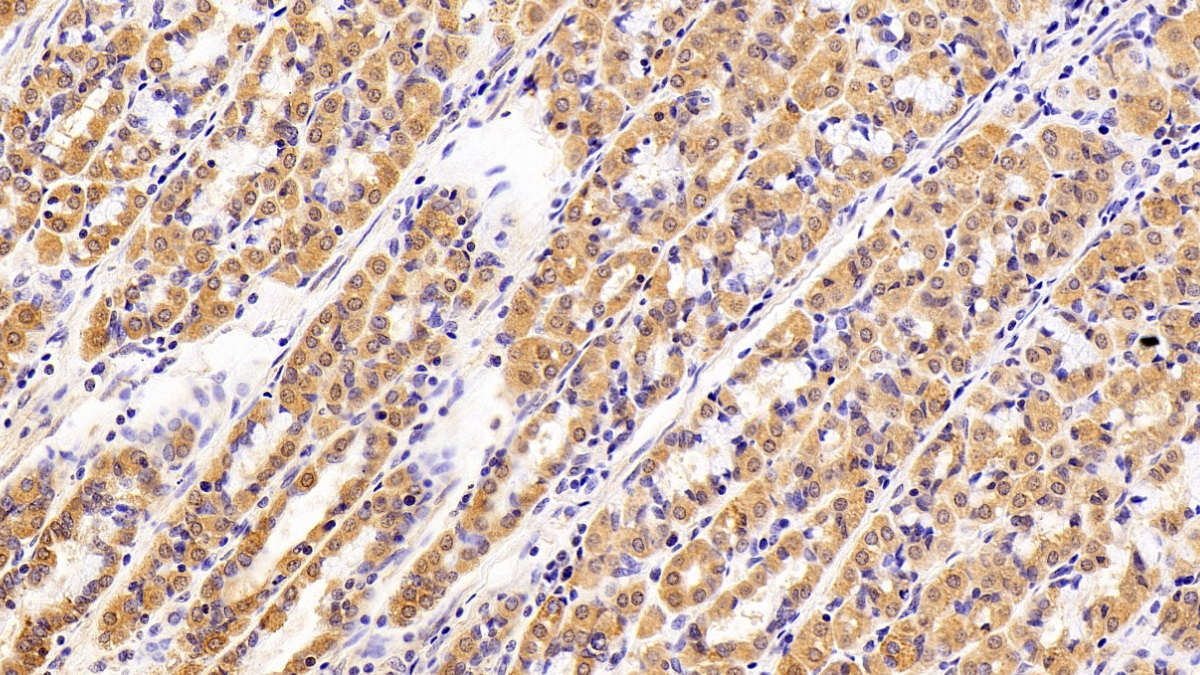

| Валидировано для | IHC WB Иммуногистохимия; Вестерн-блоттинг |

| Рекомендуемые разведения | WB: 0.2-3 мкг/мл; IHC: 2-30 мкг/мл; ICC: 2-30 мкг/мл; Оптимальное разведение определяется конечным потребителем |